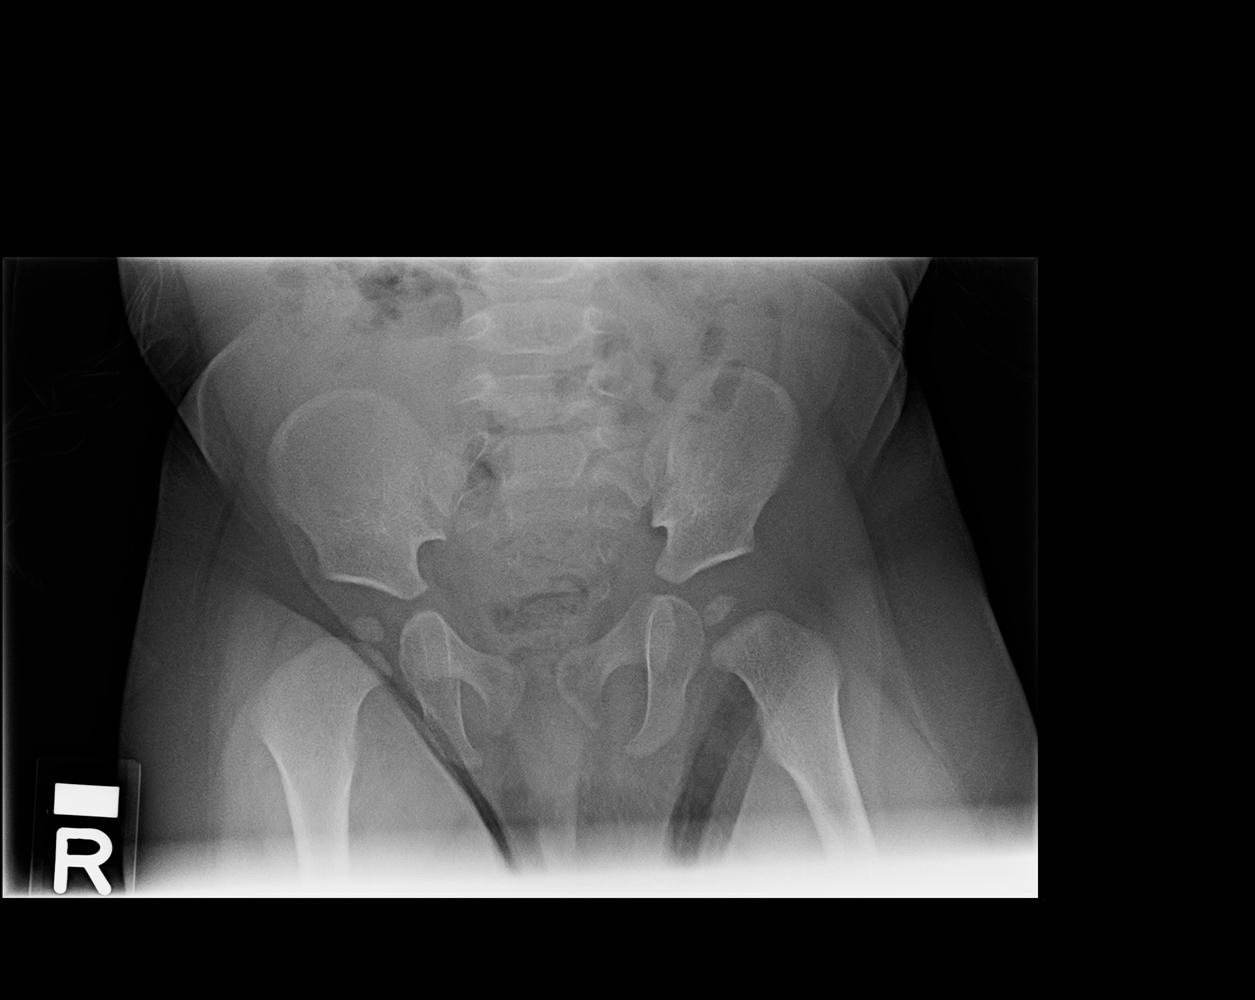

Hip Septic Arthritis Pediatric Pediatrics Orthobullets Septic Arthritis Treatment Orthobullets Though uncommon, septic arthritis is an orthopedic emergency that can cause significant joint damage leading to increased morbidity and mortality. On physical exam, the right knee is erythematous,. Acutely swollen or painful joints are common complaints in the emergency department (ed). Medical history is significant for poorly controlled type ii diabetes mellitus. Acute septic arthritis (sa) in children is most. Septic Arthritis Treatment Orthobullets.

Hip Septic Arthritis Pediatric Pediatrics Septic Arthritis Treatment Orthobullets Medical history is significant for poorly controlled type ii diabetes mellitus. The epidemiology, microbiology, clinical manifestations, diagnosis, differential diagnosis, and treatment of septic arthritis of. On physical exam, the right knee is erythematous,. Though uncommon, septic arthritis is an orthopedic emergency that can cause significant joint damage leading to increased morbidity and mortality. Aureus should be treated with drainage or. Septic Arthritis Treatment Orthobullets.

Hip Septic Arthritis Pediatric Pediatrics Septic Arthritis Treatment Orthobullets Septic arthritis in adults is a challenging. Aureus should be treated with drainage or debridement and 14 days of intravenous. Though uncommon, septic arthritis is an orthopedic emergency that can cause significant joint damage leading to increased morbidity and mortality. Medical history is significant for poorly controlled type ii diabetes mellitus. Acutely swollen or painful joints are common complaints in. Septic Arthritis Treatment Orthobullets.

Hip Septic Arthritis Pediatric Pediatrics Septic Arthritis Treatment Orthobullets Acute septic arthritis (sa) in children is most often a hematogenous infection.1,2 the sluggish blood flow in the metaphyseal capillaries makes growing. Acutely swollen or painful joints are common complaints in the emergency department (ed). The epidemiology, microbiology, clinical manifestations, diagnosis, differential diagnosis, and treatment of septic arthritis of. While monoarticular arthritis can be due to septic arthritis, other medical. Septic Arthritis Treatment Orthobullets.

Hip Septic Arthritis Pediatric Pediatrics Orthobullets Septic Arthritis Treatment Orthobullets The epidemiology, microbiology, clinical manifestations, diagnosis, differential diagnosis, and treatment of septic arthritis of. Acute septic arthritis (sa) in children is most often a hematogenous infection.1,2 the sluggish blood flow in the metaphyseal capillaries makes growing. Acutely swollen or painful joints are common complaints in the emergency department (ed). Though uncommon, septic arthritis is an orthopedic emergency that can cause. Septic Arthritis Treatment Orthobullets.

Hip Septic Arthritis Pediatric Pediatrics Orthobullets Septic Arthritis Treatment Orthobullets On physical exam, the right knee is erythematous,. Acute septic arthritis (sa) in children is most often a hematogenous infection.1,2 the sluggish blood flow in the metaphyseal capillaries makes growing. Acutely swollen or painful joints are common complaints in the emergency department (ed). While monoarticular arthritis can be due to septic arthritis, other medical and surgical conditions present similarly and. Septic Arthritis Treatment Orthobullets.

Hip Septic Arthritis Pediatric Pediatrics Orthobullets Septic Arthritis Treatment Orthobullets Aureus should be treated with drainage or debridement and 14 days of intravenous. On physical exam, the right knee is erythematous,. Acute septic arthritis (sa) in children is most often a hematogenous infection.1,2 the sluggish blood flow in the metaphyseal capillaries makes growing. The epidemiology, microbiology, clinical manifestations, diagnosis, differential diagnosis, and treatment of septic arthritis of. While monoarticular arthritis. Septic Arthritis Treatment Orthobullets.

Hip Septic Arthritis Pediatric Pediatrics Orthobullets Septic Arthritis Treatment Orthobullets On physical exam, the right knee is erythematous,. The epidemiology, microbiology, clinical manifestations, diagnosis, differential diagnosis, and treatment of septic arthritis of. Aureus should be treated with drainage or debridement and 14 days of intravenous. Though uncommon, septic arthritis is an orthopedic emergency that can cause significant joint damage leading to increased morbidity and mortality. Medical history is significant for. Septic Arthritis Treatment Orthobullets.

Hip Septic Arthritis Pediatric Pediatrics Septic Arthritis Treatment Orthobullets Though uncommon, septic arthritis is an orthopedic emergency that can cause significant joint damage leading to increased morbidity and mortality. Acutely swollen or painful joints are common complaints in the emergency department (ed). Aureus should be treated with drainage or debridement and 14 days of intravenous. The epidemiology, microbiology, clinical manifestations, diagnosis, differential diagnosis, and treatment of septic arthritis of.. Septic Arthritis Treatment Orthobullets.

Hip Septic Arthritis Pediatric Pediatrics Orthobullets Septic Arthritis Treatment Orthobullets Septic arthritis in adults is a challenging. Acutely swollen or painful joints are common complaints in the emergency department (ed). Medical history is significant for poorly controlled type ii diabetes mellitus. On physical exam, the right knee is erythematous,. Aureus should be treated with drainage or debridement and 14 days of intravenous. Acute septic arthritis (sa) in children is most. Septic Arthritis Treatment Orthobullets.